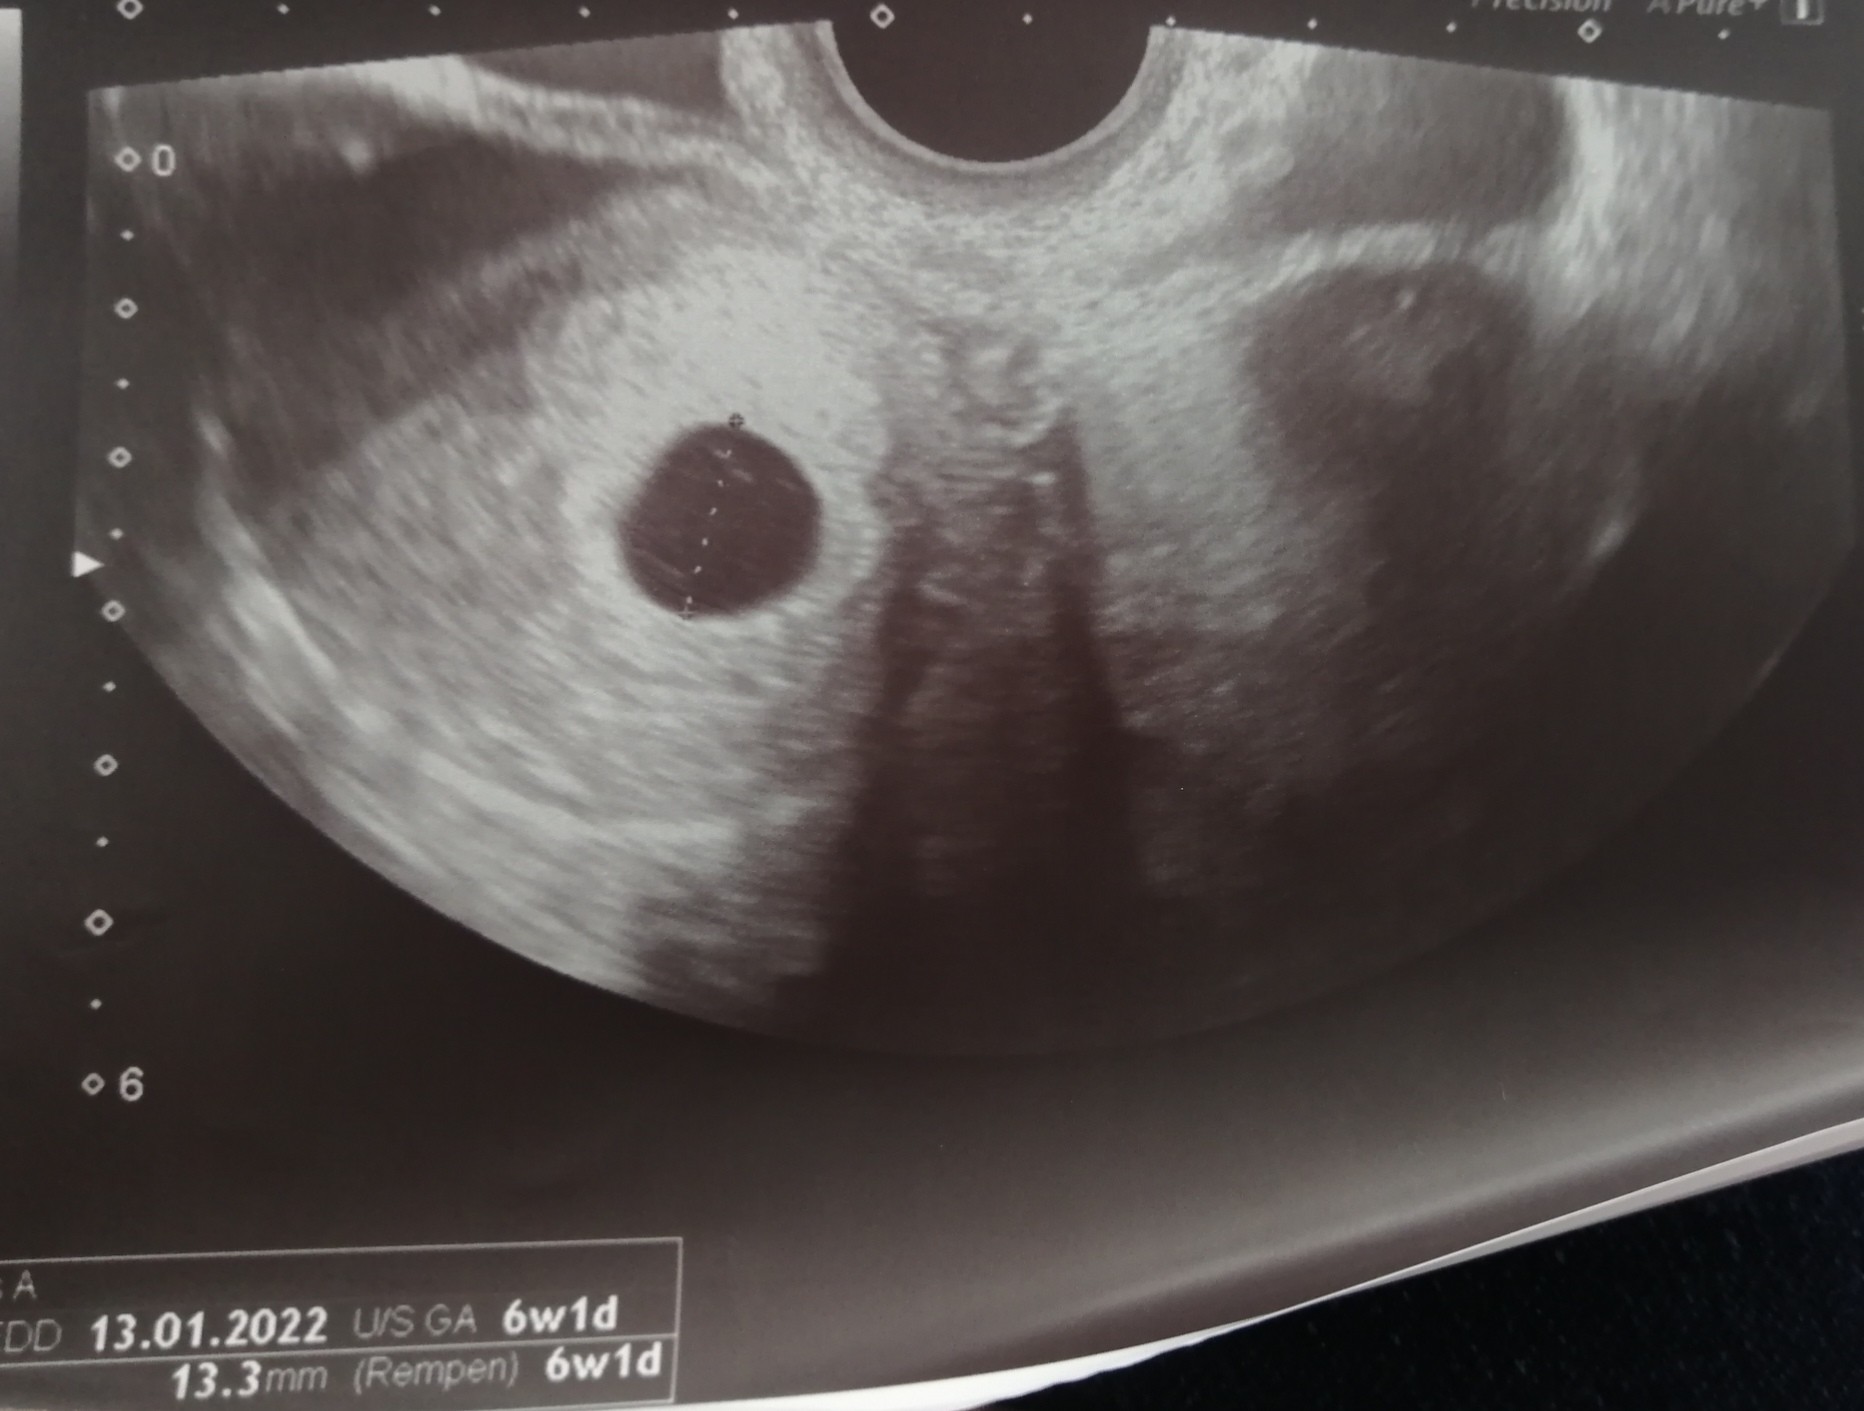

Byłam! Jest pęcherzyk ciążowy i żółtkowy. Lekarz powiedział, że dalej odrobinę za wcześnie. Mówi, że jakby widzi coś przyklejonego w tym jaju ale nie widzi na 100%. Na tą chwilę jest 6tydzien, ale podobno może się to zmienić jak się pojawi dziecko. Za 2 tyg kolejna wizyta. :o znowu tyle czekania. Jednak z tego co mówił doktor wyglądał na optymistycznie nastawionego

• IMG_20210521_141507.jpg

IMG_20210521_141507.jpg

259,9 KB · Wyświetleń: 65